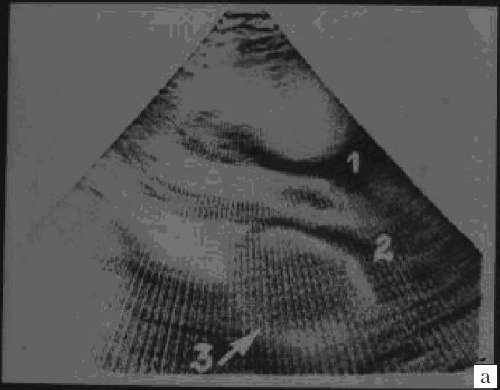

Миксомы построены из перегруженных липидами многоядерных клеток, погруженных в миксоидную строму, богатую гликозаминогликанами. Клетки располагаются группами вокруг сосудов. В 10% случаев в опухоли обнаруживаются депозиты кальция. Миксомы свойственны подросткам (рис. 3), у детей встречаются редко. Более 80% всех миксом исходят из межпредсердной перегородки и митрального клапана. Миксома может быть как спорадической (90% случаев), так и семейной опухолью (10%), наследуемой аутосомно-доминантно (миксомный синдром) в рамках синдрома Карнея [3, 4]. При семейном варианте миксома обычно множественная и склонна к рецидивированию [5, 6].

Рис. 3. Миксома левого предсердия.

а) 1 и 2 - стенка аорты, 3 - миксома.

б) Макропрепарат удаленной миксомы.